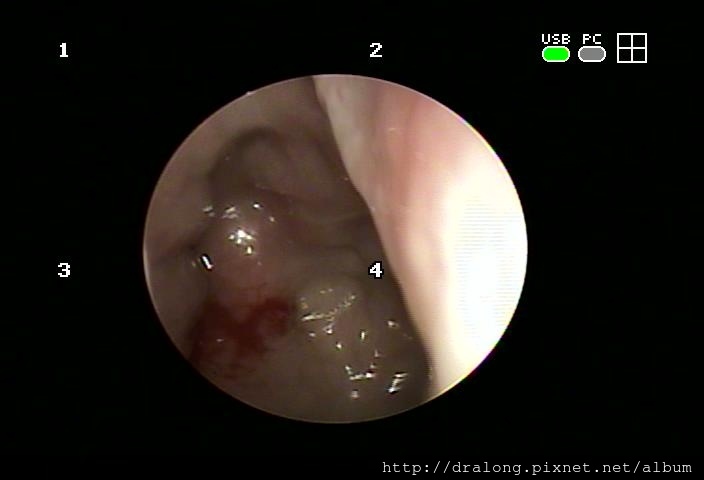

急性鼻咽發炎